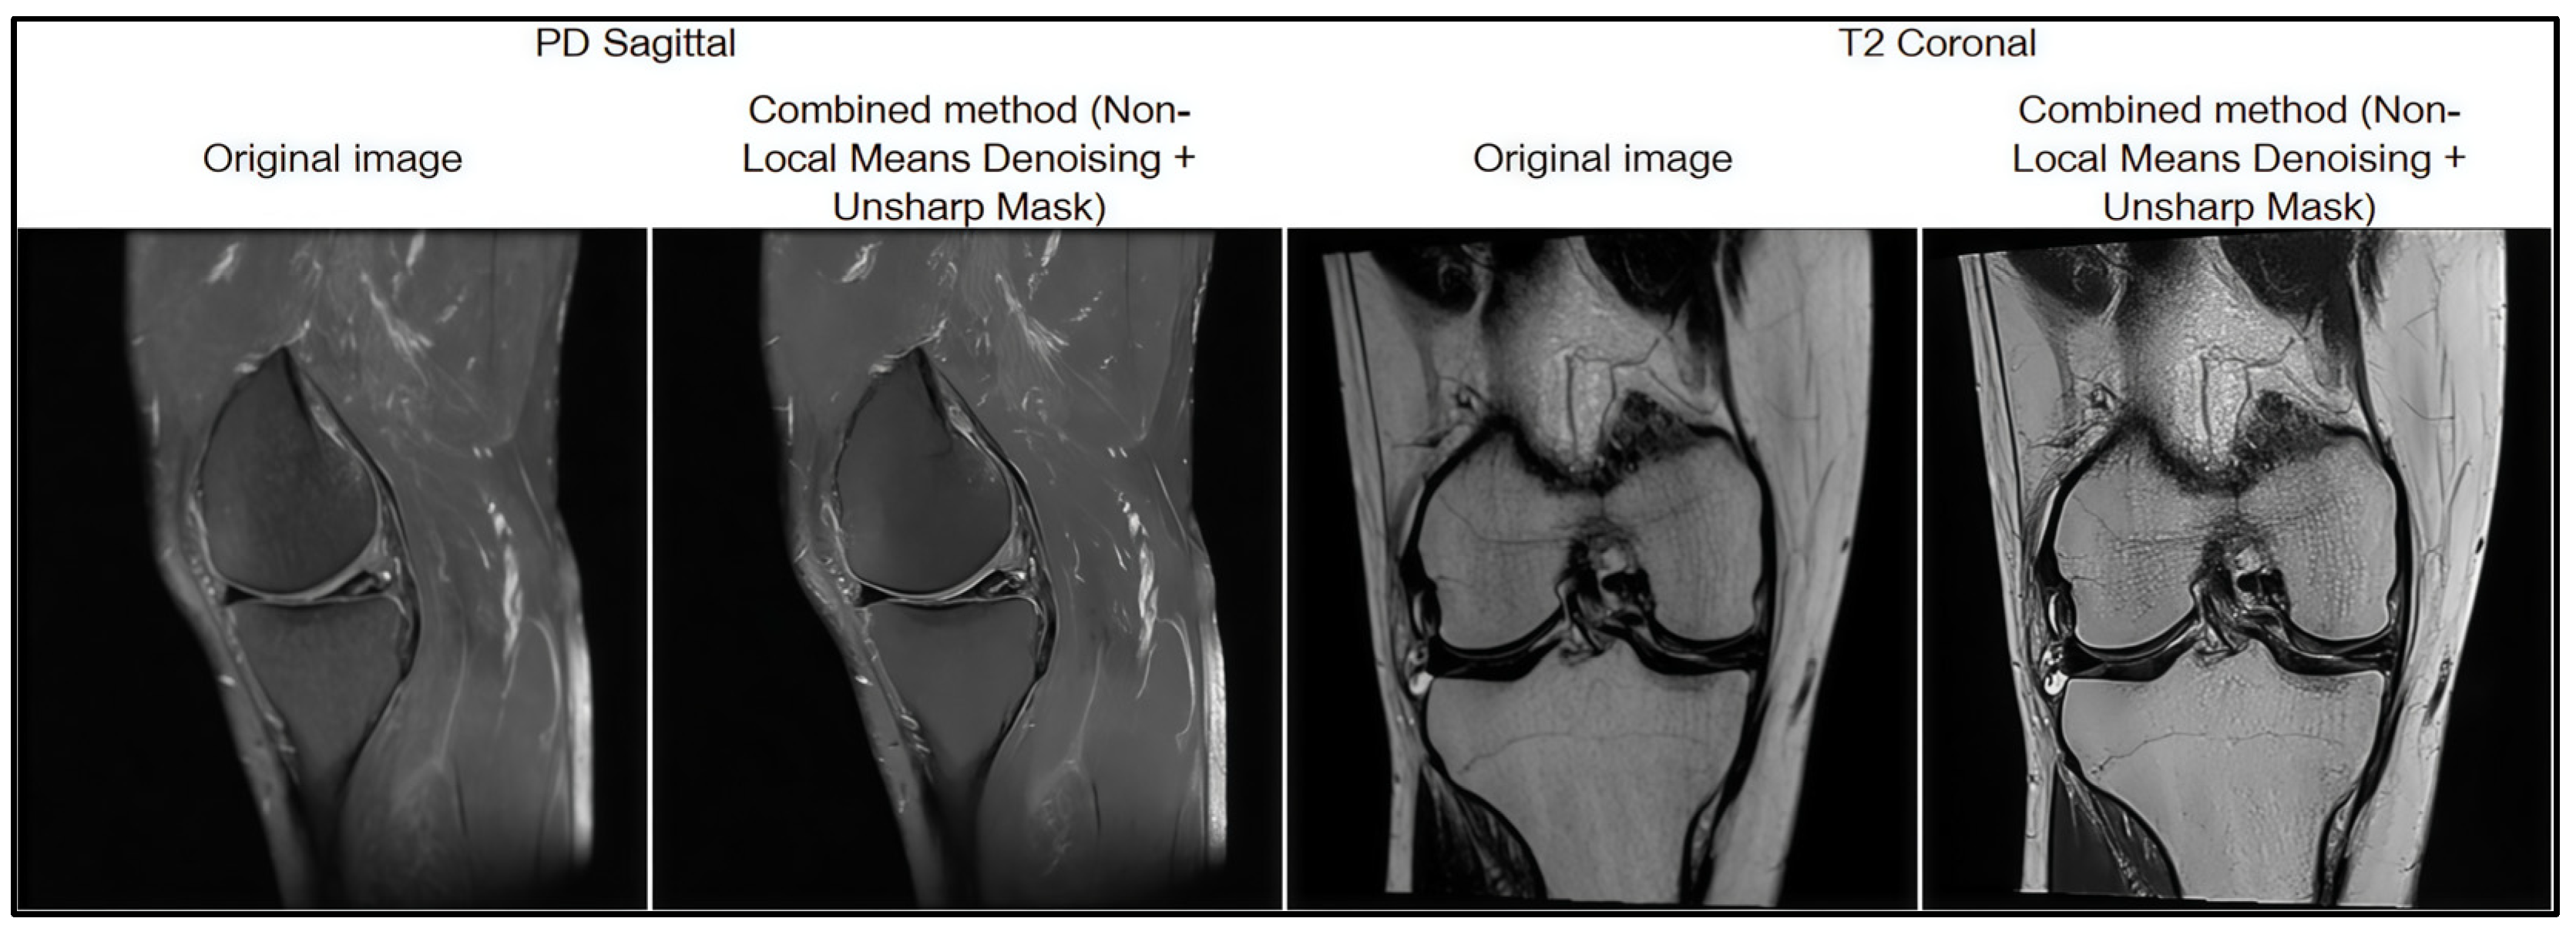

3.4. Data Preprocessing

- Using different imaging modes (PD, T1, T2). MRI images acquired in different imaging modes such as PD, T1, and T2 were used in the study. Each of these modes has different contrast features and displays tissue structures differently. As a result, signs of rupture could be visualized with different degrees of severity depending on the imaging mode, which placed additional burden on the model and reduced the stability of classification between cases acquired in different imaging settings.

| Method | MSE | PSNR | SSIM |

| Combined method | 32.55 | 41.37 | 0.92 |

| Gaussian Blur | 39.47 | 39.36 | 0.90 |

| Laplacian Filter | 39.80 | 38.21 | 0.90 |

| Bilateral Filter | 35.45 | 39.76 | 0.86 |

| Non-Local Means Denoising (NLM) | 35.69 | 39.57 | 0.86 |

| Sharpening (Unsharp Mask) | 47.10 | 35.80 | 0.85 |

| Median Blur | 42.20 | 32.26 | 0.82 |

| CLAHE | 132.33 | 24.47 | 0.74 |

| Sobel Filter | 190.83 | 21.22 | 0.68 |